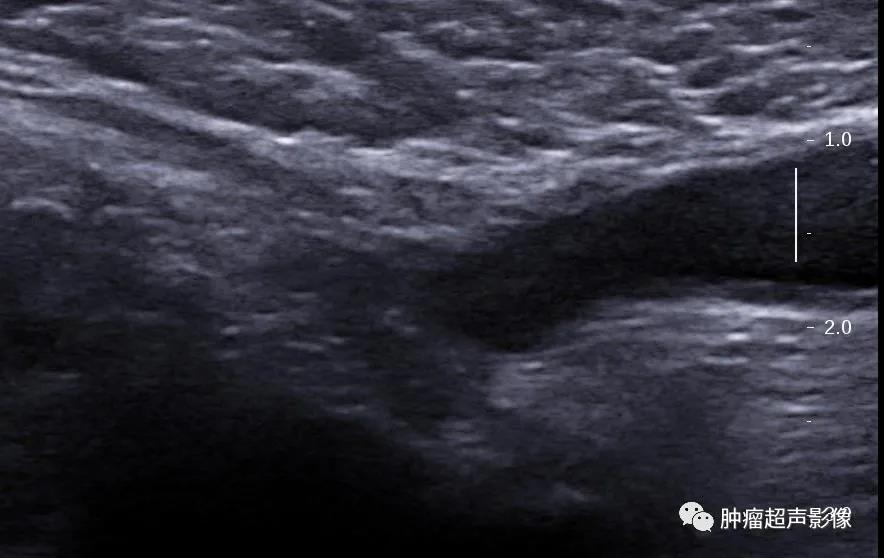

3、睾丸精索鞘膜积液:阴囊内无回声区从三面包绕睾丸,纵切面呈梨形,并向上延伸至精索,其上端较窄。

睾丸精索鞘膜积液